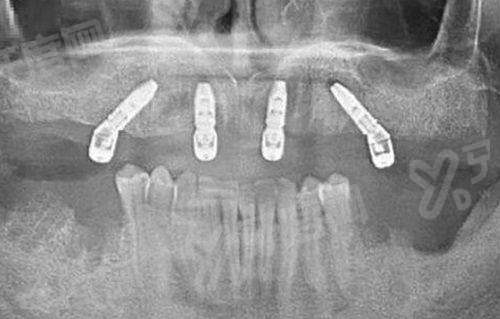

√ 淮南安美口腔所用的奥齿泰种植体可以提供多种种植体系统,适用于不同的临床需求,包括标准种植体、窄直径种植体、短种植体等,满足不同患者的解剖结构和治疗需求。

√ 士卓曼适用于单颗牙缺失、多颗牙缺失乃至全口无牙颌的修复,同时,士卓曼提供多样化的修复组件,确保修复成效既美观又功能性强。

4、瑞士士卓曼亲水种植体价格:10800元起/颗

√ 士卓曼的亲水种植体表面进一步优化了与周围组织的相互作用,提高了手术中的操作便利性和术后愈合效率。